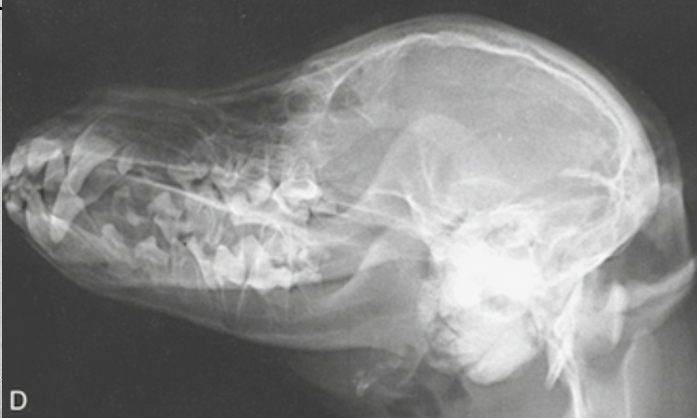

7

Q

whats this

A

Oblique mandibular view.